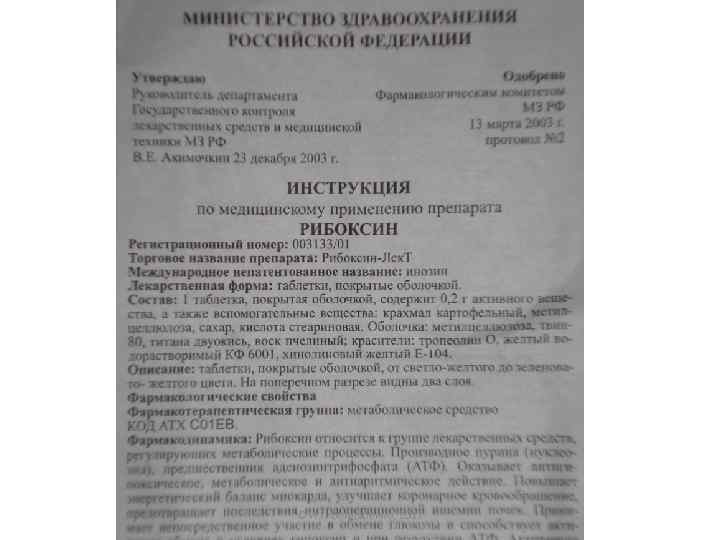

Активаторы ксантиноксидоредуктазы • Рибоксин (инозин) • Молибден • Медь • Железо • Рибофлавин-5 -фосфат 25

Показания к применению. Препарат применяется в комплексном лечении ишемической болезни сердца, состояний после инфаркта миокарда, врожденных и приобретенных пороков сердца, при нарушениях ритма сердца, особенно при гликозидной интоксикации, миокардитах, дистрофических изменениях миокарда после перенесенных тяжелых физических нагрузок и инфекционных болезней; гепатитах, циррозах печени, в том числе вызванных алкогольной или лекарственной интоксикациями; профилактике лейкопении при радиоактивном облучении. Способ применения и дозы. Взрослые принимают по одной таблетке внутрь до еды, 3 -4 раза в день, не разжевывая, запивая большим количеством жидкости. Суточная доза составляет 0, 6 -0, 8 г. При хорошей переносимости дозу постепенно увеличивают до 1, 2 г в сутки в 3 -4 приёма, при необходимости — до 2, 4 г в сутки. Побочное действие. Препарат обычно хорошо переносится. В отдельных случаях может возникнуть зуд и гиперемии кожи, в редких случаях — повышение концентрации мочевой кислоты в крови. При длительном применении в больших дозах возможно обострение подагры. 36